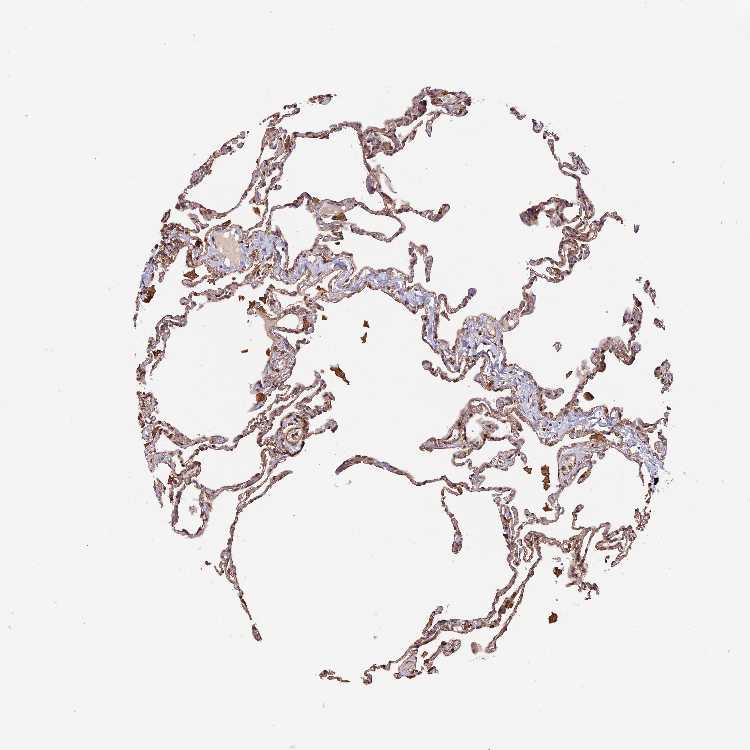

LUNG - Antibody stainingi

Antibody staining in the annotated cell types in the current human tissue is reported as not detected, low, medium, or high, based on conventional immunohistochemistry profiling in selected tissues. This score is based on the combination of the staining intensity and fraction of stained cells.

Each image is clickable and will lead to virtual microscopy that enables deeper exploration of all samples and also displays staining intensity scores, fraction scores and subcellular localization as well as patient and tissue information for each sample.

Antibody HPA040390Antibody CAB002611

Alveolar cells MediumNot detected

Macrophages HighMedium